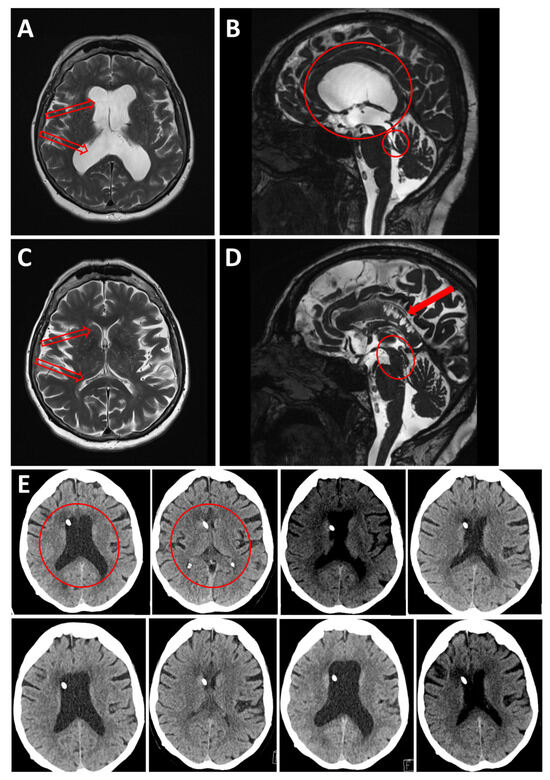

A 63-year-old woman underwent a ventriculoperitoneal (VP) shunt procedure for triventricular hydrocephalus due to Sylvian aqueduct stenosis (Figure 3A,B). Four months after VP shunt implantation, she developed psychomotor retardation and cognitive disorders, particularly memory impairment, along with apathy and difficulty walking. A few months later, she developed vertical gaze palsy. CT and MRI scans (Figure 3C,D) showed a shrinkage of the ventricular system, resulting in slit ventricles, an elongation of the midbrain, and callosal infarction. Although valve settings were adjusted, this rapidly led to the reformation of slit ventricles. After three cycles of dilated and collapsed ventricles over ten days and difficulty in finding the correct drainage setting, the patient received an assist shunt, which finally normalized the ventricle size and restored normal vigilance, though vertical gaze palsy persisted.

Figure 3. Case 2: (A) Axial and (B) Sagittal T2-weighted MRI showing triventricular hydrocephalus (red empty arrows on (A); large red circle on (B)) due to Sylvian aqueduct stenosis (small red circle on (B)). (C) Axial and (D) Sagittal T2-weighted MRI showing shrinkage of the ventricular system, resulting in slit ventricles (red empty arrows on (C)), elongation of the midbrain (red oval on (D)) and callosal infarction (full red arrow on (D)) due to its compression against the falx. (E) Illustration of the rapid alternating ballooning (e.g.: red circle on first upper left panel) and shrinking (e.g.: red circle on second upper left panel) of the ventricles over a short period of time (September through November 2019), due to alternating overdrainage and underdrainage. First image, upper left: four days post shunt placement. The following images represent the different adjustments of valve pressure.